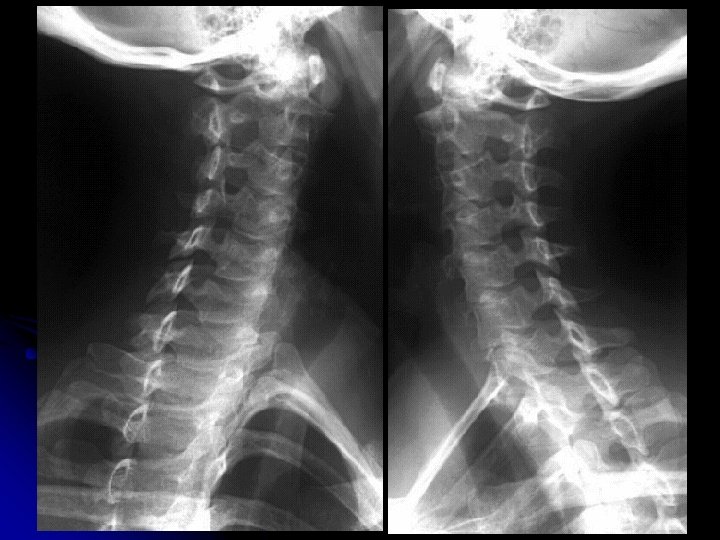

Rachis cervical

l Critères de réussite : l superposition des angles mandibulaires, des apophyses articulaires droites et gauches l Absence de dédoublement des murs postérieurs l Dégagement de tous les interlignes discaux et articulaires postérieurs l Visualisation de tout le rachis cervical jusqu'en C 7 -T 1

c 2 Articulaire supérieure lame Processus épineux Articulaire inférieure c 7 T 1 Disque intervertébral

l Résultats: l Etude de la courbure rachidienne l Structure et morphologie des corps vertébraux l Alignement des murs postérieurs l Hauteur des espaces intervertébraux l Position et morphologie des arcs postérieurs l Ligne spino-laminaire l Diamètre antéro-postérieur du canal cervical l Epaisseur des parties molles pré-vertébrales